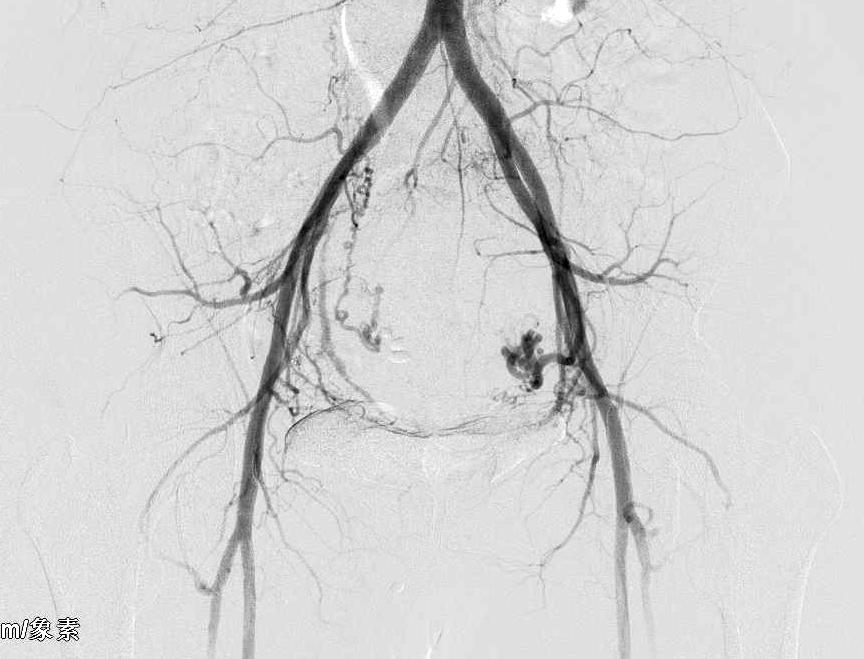

8月16日早8时手术开始,在医护默契配合下,手术历时三十五分钟,异常供血的子宫动脉血管被全部封堵栓塞,手术成功,术后患者由护理人员搀扶走出手术室。

术后,患者和家属激动地握着医护人员的手说:“没想到还有这么好的治疗,免去了我多年的担忧,怎么感谢你们呢!”谢纱耐心叮嘱患者术后注意事项、观察要点,护士长白小爱及责任护士指导患者饮食、活动及复诊,电话随访。苏女士月经如期而至,疼痛明显缓解,月经期量基本恢复正常,复查血色素持续升高,三个月后复查效果高出预期,超声检查提示子宫恢复正常大小,肌瘤消失。